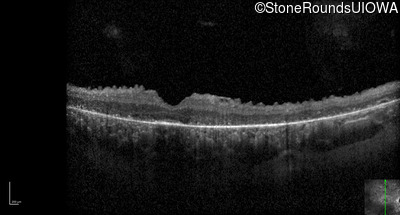

Optical Coherence Tomography - Left - 5/140 sc

Exemplar / OCT Stack